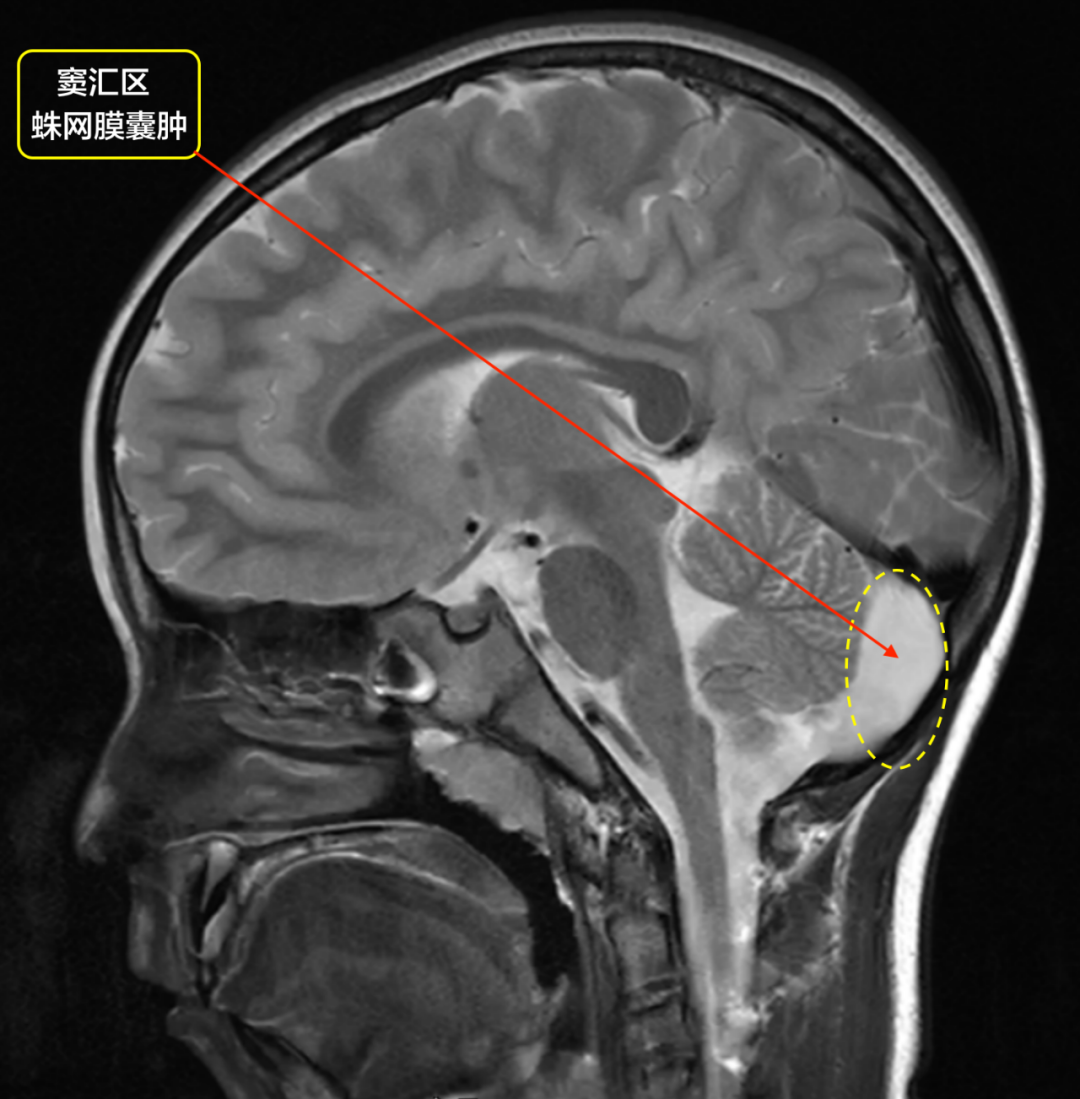

一网打尽颅内非肿瘤性囊肿!

什么是颅内蛛网膜囊肿?

颅内蛛网膜囊肿有什么症状?